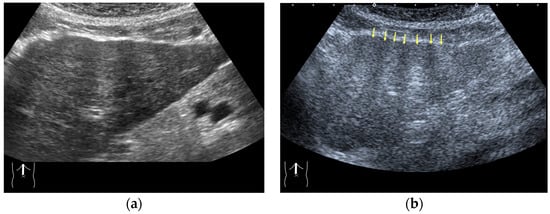

3.1.2. Attenuation Artifacts

There are two sources of sound attenuation in the human body, (a) reflection and sound scattering and (b) sound absorption [47]. Both factors contribute to the formation of attenuation artifacts. These artifacts mainly occur in difficult patients (e.g., patients with advanced liver cirrhosis, patients with obesity, and patients with severe fatty liver) [48,49,50]. Increasing the mechanical index (M.I.) is not recommended for overcoming this attenuation artifact because an excessively increased M.I. causes visible microbubble destruction at the hepatic surface. Generally speaking, US attenuation in soft tissues is highly dependent on the US frequency and is nearly proportional to it (Figure 6). Less attenuation with a lower frequency results in an increased penetration depth. Thus, the most useful strategy is to use a transducer with a lower transmission frequency at the expense of a slightly deteriorated image quality (Figure 7). Another diagnostic strategy is to adjust the STC 3), which slightly improves the visualization of deep areas (Figure 8). We present herein a representative case of a “pseudo-tumor” in a decompensated cirrhotic patient where less attenuated US beams passing through the ascites mimicked an echogenic tumor at the periphery of the liver not only in B-mode US but also in CEUS (Figure 9).

Figure 9.

Representative case of a sound attenuation artifact. The presence of massive ascites leads to US beams passing through less attenuated ascites, mimicking an echogenic liver tumor (arrows). (a) B-mode US and (b) CEUS.